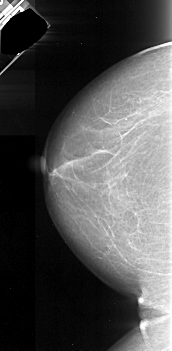

A_1048_1.RIGHT_MLO

RIGHT_MLO LINES 4846 PIXELS_PER_LINE 2506 BITS_PER_PIXEL 16 RESOLUTION 42 OVERLAY

FILE: A_1048_1.RIGHT_CC.OVERLAY

TOTAL_ABNORMALITIES 1

ABNORMALITY 1

LESION_TYPE MASS SHAPE IRREGULAR MARGINS ILL_DEFINED

ASSESSMENT 4

SUBTLETY 5

PATHOLOGY MALIGNANT

TOTAL_OUTLINES 1

BOUNDARY